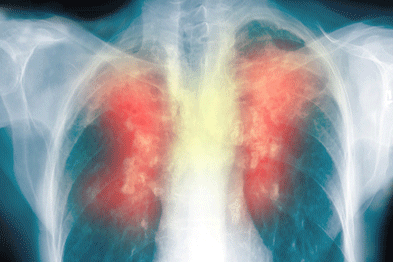

Τι είναι η Χρόνια Αποφρακτική Πνευμονοπάθεια;

Με τον όρο ΧΑΠ περιγράφουμε μία ομάδα χρόνιων πνευμονικών παθήσεων (την χρόνια βρογχίτιδα και το πνευμονικό εμφύσημα) οι οποίες έχουν κοινό παρονομαστή τον προοδευτικό περιορισμό της ροής του αέρα στους βρόγχους και επακόλουθη δυσκολία στην αναπνοή.

Η χρόνια βρογχίτιδα ανήκει στη ΧΑΠ. Χαρακτηρίζεται από φλεγμονή και μεγάλη παραγωγή βλέννας μέσα στους βρόγχους με στένωση των βρόγχων, βήχα, και φλέγματα. Είναι η πάθηση κατά την οποία ο ασθενής , καπνιστής συνήθως, έχει παραγωγικό βήχα, δηλαδή βήχα με πτύελα, για τις περισσότερες μέρες τριών συνεχόμενων μηνών και για δύο συνεχόμενα χρόνια. Πρέπει, βέβαια, να αποκλειστούν άλλες αιτίες παραγωγικού βήχα, όπως είναι ο καρκίνος των πνευμόνων, οι βρογχιεκτασίες, η φυματίωση, οι συχνές λοιμώξεις των πνευμόνων κ.α.

Τι είναι το Πνευμονικό εμφύσημα;

Το εμφύσημα ξεκινά με την καταστροφή των κυψελίδων των πνευμόνων. Οι κυψελίδες είναι οι φυσαλίδες στην επιφάνεια του πνεύμονα όπου γίνεται η ανταλλαγή του οξυγόνου της ατμόσφαιρας με το διοξείδιο του άνθρακα που παράγεται στο σώμα μας από τις καύσεις. Η καταστροφή αυτή είναι μη αντιστρεπτή και καταλήγει σε διάταση και στη δημιουργία μόνιμων τρυπών στον ιστό των πνευμόνων. Καθώς καταστρέφονται οι κυψελίδες, οι πνεύμονες μεταφέρουν όλο και λιγότερο οξυγόνο προς την κυκλοφορία του αίματος, προκαλώντας βράχυνση (συντόμευση) της αναπνοής. Χάνεται, επίσης, η ελαστικότητα του πνεύμονα, η οποία είναι υπεύθυνη για να κρατάει του πνεύμονες ανοιχτούς. Τα συμπτώματα του εμφυσήματος περιλαμβάνουν βήχα, δύσπνοια, βράχυνση της αναπνοής, αδυναμία και περιορισμένη αντοχή στην άσκηση. Καθώς η νόσος εξελίσσεται, το έργο της αναπνοής (δηλαδή η προσπάθεια που καταβάλει ο ασθενής για να αναπνεύσει) γίνεται τόσο μεγάλο, που οδηγεί σε μεγάλη απώλεια βάρους.Τα συμπτώματα ξεκινούν στην ηλικία των 35-40 ετών με τον λεγόμενο ‘τσιγαρόβηχα’ με τον οποίο μπορεί να αποβάλλονται πτύελα. Κάποιες φορές ο καπνιστής μπορεί να αισθάνεται την αναπνοή του να ‘σφυρίζει’, ενώ τα κρυολογήματα γίνονται πιο συχνά. Σε αυτή τη φάση εάν το άτομο δεν δώσει σημασία στα συμπτώματα αυτά , και συνεχίζει να καπνίζει, μετά από λίγα χρόνια προστίθεται η δυσκολία στην αναπνοή (δύσπνοια), αρχικά στο γρήγορο βάδισμα, στην ανηφόρα ή στο ανέβασμα σκάλας. Από εκεί και μετά η κατάσταση χειροτερεύει γρήγορα. Γύρω στην ηλικία των 55-60 ετών η δύσπνοια θα έχει επιδεινωθεί τόσο που ο ασθενής θα δυσκολεύεται να κάνει δουλείες ακόμη και μέσα στο σπίτι του.